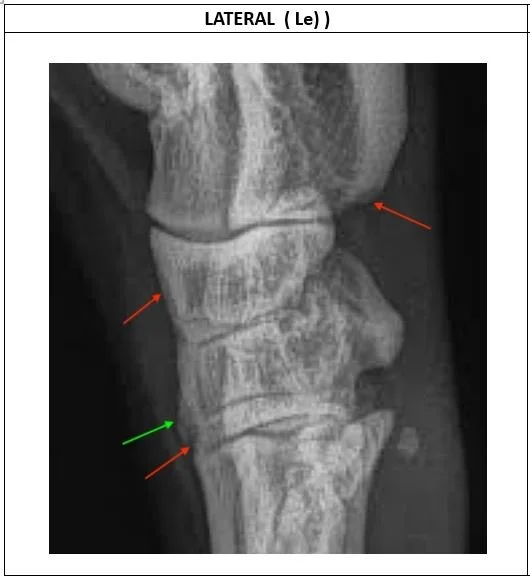

Plantar lesion – red arrow points to cortical lysis of calcaneus. There is hint of soft tissue calcification just distal to this arrow. This may indicate that the plantar ligaments have been damaged and are now over-contracted.

Dorsal (forward facing) lesions include

• lysis in cortex of CTB (red arrow)

• excess callus base of T3 (green arrow)

• lysis at interface of T3 and MT3 (red arrow).

These changes in the dorsum may indicate that there is overload due to weight and increased torsional strain. This may occur with laxity of the dorsal soft tissues.

Mild cortical lysis in distal talus (red arrow) which may be due to over-stretching of soft tissues and is common but rarely any problem.

Green arrow points to increased whiteness (sclerosis) in top of metatarsal III which is associated with vertical weight and torsional stress.

There is a vertical fracture line in T4 (marked with red arrows).